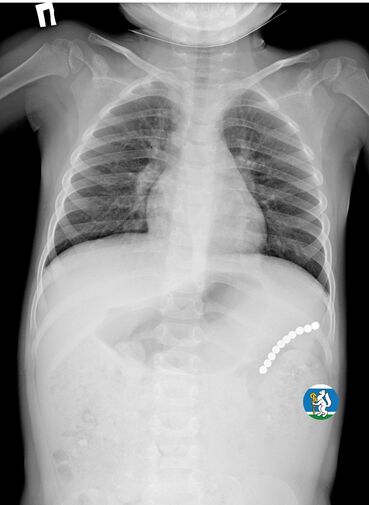

Девочка рассказала родителям о плохом самочувствии, и те показали ее врачам. Медики направили пациентку на рентген грудной клетки. Благодаря обследованию специалисты обнаружили в проекции желудка цепочку магнитов, соединенных между собой. Ребенку сразу же госпитализировали и оказали помощь.

«Для минимизации риска осложнений удаление инородных тел было проведено интраоперационно. В ходе вмешательства дежурная бригада врачей извлекла 10 магнитных шариков, цепочка которых в длину составила 5 сантиметров», — рассказал детский хирург ДГКБ №9 Андрей Чукреев.